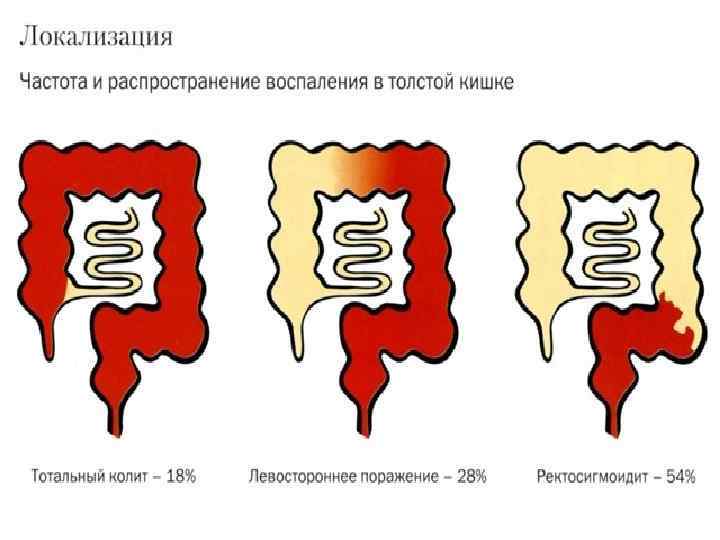

Локализация язвенного колита Поперечноободочная 33. 1 % Восходящая 27. 1 % Слепая 10. 5% Нисходящая 46. 6% Сигмовидная 80. 1% Прямая 99. 6 % На момент установления диагноза: 40%- поражена только прямая кишка 50%- левосторонний колит 10%- тотальный колит

Локализация язвенного колита Поперечноободочная 33. 1 % Восходящая 27. 1 % Слепая 10. 5% Нисходящая 46. 6% Сигмовидная 80. 1% Прямая 99. 6 % На момент установления диагноза: 40%- поражена только прямая кишка 50%- левосторонний колит 10%- тотальный колит